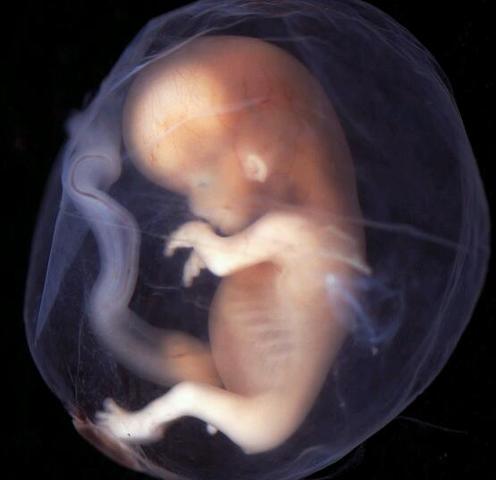

• heartbeat

heartbeat

During this time the heartbeat grows stronger and other body systems become further developed. The fingernails, hair, eyelashes and toenails form and most noticeably. this domain is physical

• size

size

By now the fetus has increased dramatically in size, about six times in size. The brain and central nervous system also become responsive during this time. this domain is physical

• mature

mature

The brain starts to mature much faster with the activity that greatly resembles a sleeping newborn. The fetus continues to develop, put on weight, and prepare for life outside of the womb. The lungs begin to expand and contract, preparing the muscles for breathing. this domain is physical